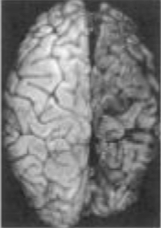

Apa yang ditunjukkan oleh spesimen kasar di bawah ini

A. Sklerosis Majemuk

B. Kern Ikterus

C. Nekrosis Laminar

D. Zat abu Heterotopic

E. emboli Lemak

C